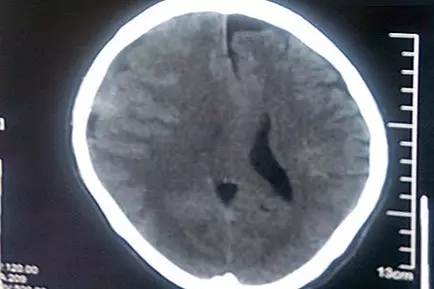

老馮才告訴了家人。縣醫(yī)院CT診斷結(jié)果比他想象的嚴(yán)重得多!這大樹(shù)枝把他砸出了亞急性硬腦膜下血腫,出血量較大,腦中線已經(jīng)移位,并有腦疝風(fēng)險(xiǎn)。馬不停蹄的老馮一家到了省城的三甲醫(yī)院,接著又趕到了上海的三甲醫(yī)院,然而都以各種理由被建議轉(zhuǎn)院治療。不幸中的萬(wàn)幸是,老馮的亞急性硬腦膜下出血相比急性硬腦膜下出血,出血速度稍緩,所以血腫形成至腦受壓的過(guò)程略長(zhǎng),為老馮四處求醫(yī)爭(zhēng)取了寶貴的時(shí)機(jī)。

患者術(shù)前CT影像:腦中線結(jié)構(gòu)向左偏移